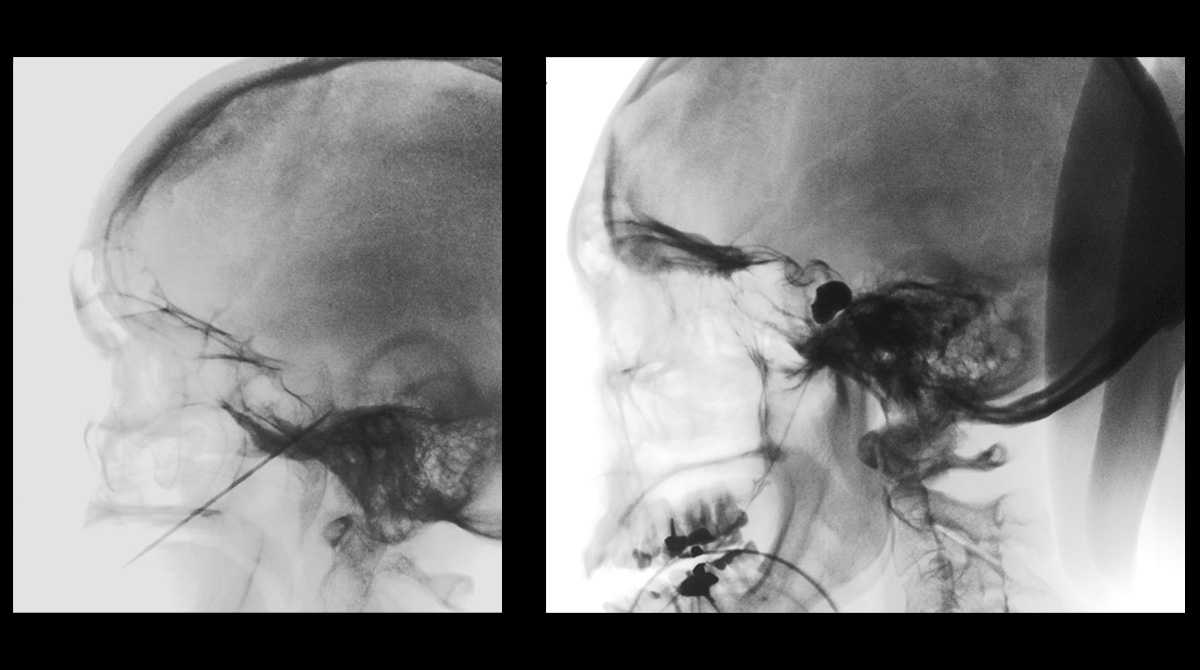

Image

Coagulation du nerf et compression du nerf à l'aide d'un ballon